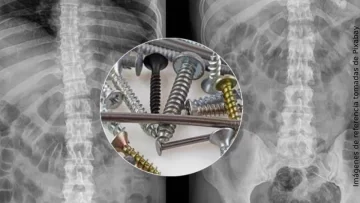

Una radiografía de su estómago mostró que en su interior había piezas metálicas de hasta 10 centímetros.

El hospital transmitió a medios locales una fotografía de una bandeja quirúrgica con los clavos y tornillos. "Nunca habíamos visto nada parecido", aseguró a la prensa Algirdas Slepavicius, jefe del servicio de cirugía del hospital de Klaipeda.